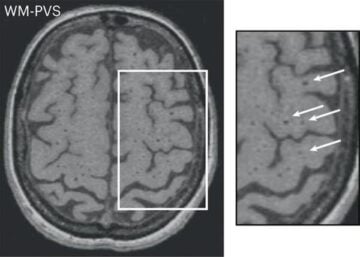

Une vaste étude génomique sur les espaces périvasculaires publiée dans la revue Nature Medicine le 17 avril 2023 révèle des mécanismes biologiques nouveaux impliqués dans la maladie des petites artères cérébrales, une des principales causes d’AVC et de démence.

Genomics of perivascular space burden unravels early mechanisms of cerebral small vessel disease (2023).